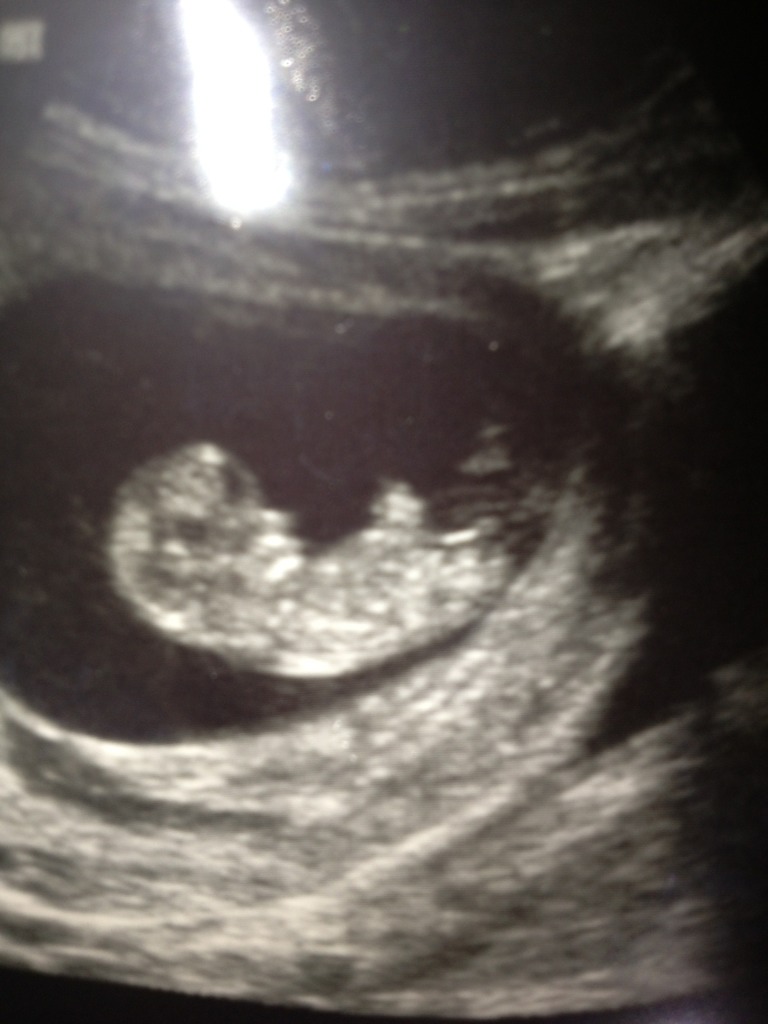

I am only 10.4 but tech said baby was measuring more like 11weeks. Anyways any nub/skull guesses or too early?Attachment 9937Attachment 9938

Yup too early... Any guess would be 50/50

first one looked like a boy nub that hasn't risen, the second one looked like a girl nub. I agree, too early either way. probably better around 12-13 weeks!

Maybe girl? But very early.